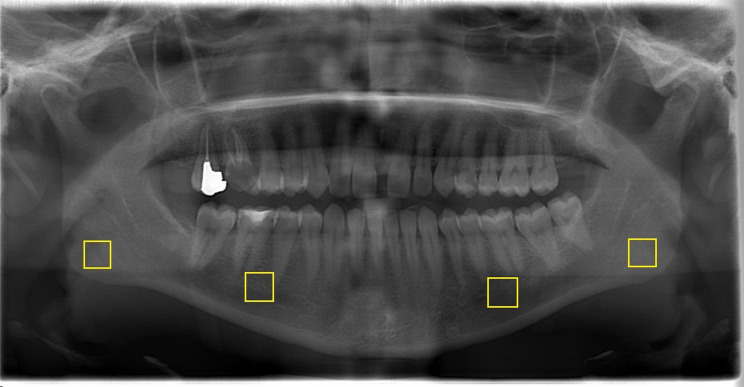

On panoramic radiographs, a total of 4 regions of interest (ROI) of 100 × 100 pixels were selected. The first ROI was from the interdental regions of the right-left mandibular second premolars and first molars (excluding the periodontium and the cortical borders of the mandibular canal) and the second ROI was from the right and left mandibular angulus (Fig. 1).

Fig. 1.

Selecting the specified ROIs on the program